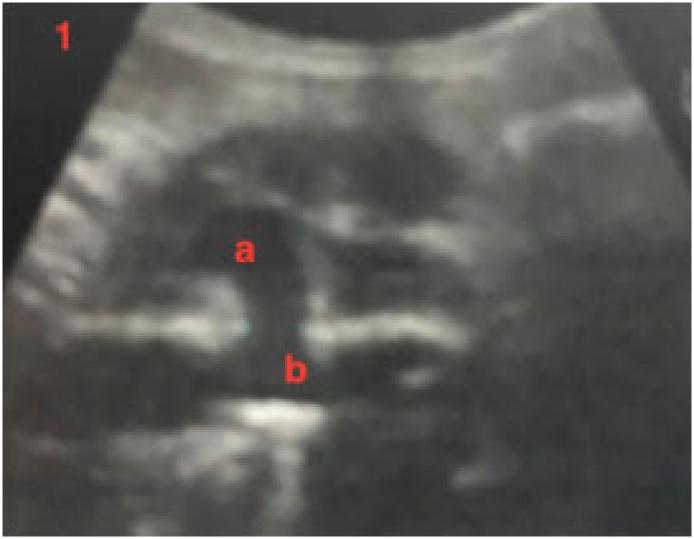

We report 2 patients with ruptures of the tuberculous aneurysm. All patients had acute abdominal pain and were diagnosed by echography then CT scan preoperatively. The first patient (male, 50 years old) had a ruptured saccular aneurysm. The second patient (male, 43 years old) had a retroperitoneal contained rupture. All were treated by open prosthetic repair, by vascular surgeons. The two patients were well after operations. The diagnosis was confirmed by pathology examination. Antituberculous treatment was introduced after the operation.

我们报告了2例结核性动脉瘤破裂患者。所有患者均有急性腹痛,术前经超声检查后行CT扫描确诊。首例患者(男性,50岁)为囊状动脉瘤破裂。第二例患者(男性,43岁)为腹膜后局限性破裂。所有患者均由血管外科医生行开放性人工血管修复术治疗。术后2例患者情况良好。病理检查确诊。术后开始抗结核治疗。